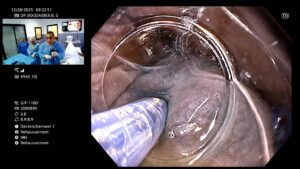

🔍 Déroulement de la procédure

- Le médecin crée un tunnel sous la muqueuse œsophagienne.

- Il sectionne les fibres musculaires du SIO responsables de l’obstruction.